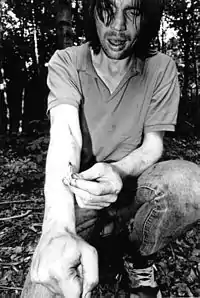

Debido a su solubilidad en disolventes orgánicos y agua, la heroína puede penetrar a través de las membranas mucosas del cuerpo. Puede ser inyectada en el cuerpo de varias maneras: a través de la mucosa nasofaríngea, el estómago, el intestino, el recto, la vagina, o también puede fumarse, inhalarse e ingerirse por vía oral. Desde el comienzo del siglo XX hasta la actualidad, el método más común de usarla era por vía intravenosa o inyectada,[52] ya que dicho consumo permite un efecto rápido e intenso. Además, al necesitarse cantidades muy bajas en el consumo por vía intravenosa, suele convertirse en un método económico mediante el que los heroinómanos pueden reducir la dosis y el costo de manera significativa. Para la administración a través de las membranas mucosas se requiere un especial refinado de la heroína, que es caro y requiere de más materiales.[56][67]

Los sujetos que presentan adicción a la heroína utilizan diferentes métodos para administración de la sustancia, entre ellos:

- Cutánea - se crea una incisión superficial en la piel, que se frota a fondo. Con este método, son características las cicatrices queloides.

- Intravenosa - Inyección; la dosis de la droga se disuelve en agua y se hierve para la esterilización y una disolución mejor. La heroína suele ser introducida en las venas superficiales de las extremidades, pero se pueden introducir en cualquiera de las venas, como en los consumidores de drogas que suelen tener grandes daños a las venas.[69]